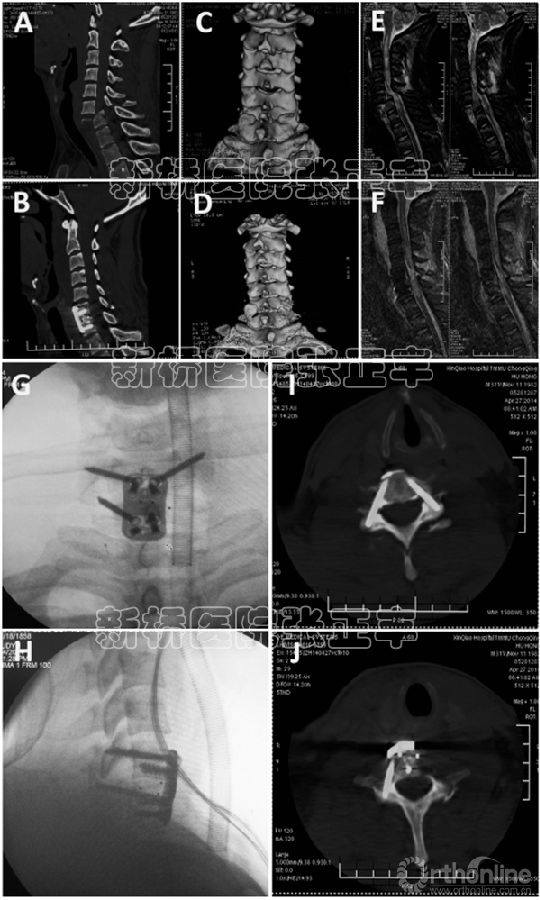

临床资料汇总见表1。平均手术时间为118分钟(范围70 - 160分钟),平均失血量为153毫升(范围50 - 210毫升)。1个节段植入2到3个椎弓根钉(C6和C7一个椎体的每侧允许植入2个)(Fig. 3);每个节段植入椎体钉4到6颗。ASIA E级和D级的病人允许次日戴颈托走动。

术后X线、MRI和CT显示颈椎序列良好,椎弓根螺钉准确置入椎弓根皮质内(Fig. 1K–P, Fig.3)。患者随访时间6个月以上,X线平片及CT扫描显示成功的脊柱融合的。没有由于技术运用而导致的并发症或内固定失败。4个ASIA A级和1个B级患者无神经功能改善;一个ASIA B级患者神经功能改善至C级;2例ASIA D级患者神经功能改善至E级;没有ASIA E级患者出现神经功能恶化。

Fig. 3. C6–C7双侧小关节脱位双侧APS固定(Case 1):(A, B)术前和术后的矢状位CT显示C6–C7脱位复位,(C, D)术前和术后的CT三维重建显示的C6–C7脱位复位,(E, F)术前和术后MRI显示脊髓T2矢状位图像的压迫和解压,(G, H)术中C5-C6钢板螺钉固定后透视图像,(I, J)术后CT显示C6双侧和C7单侧椎弓根螺钉位置固定好。

此外,它允许从C6和C7椎体两侧插入2颗APS (Fig.3),因为C6和C7进钉点位于椎体表面的同侧[11–19]。虽然C3- C5进钉点的位于中央或对侧,每一个节段从对侧植入APS是允许的(Fig. 1K–P),这样从理论上较APS同侧固定提供了更强的抗旋转[14,15,19]。